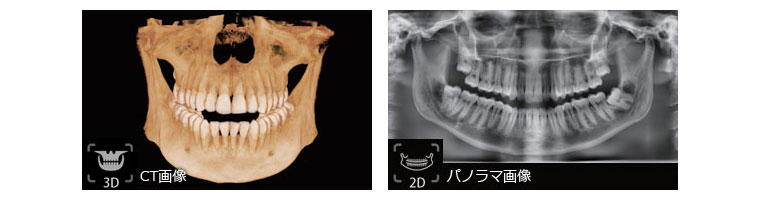

歯科用CTレントゲンは、従来の2D(2次元的な)画像だけではなく、立体的な3Dで360度の画像を撮影できるレントゲンです。

従来のレントゲンや通常のデジタルレントゲンだけでは見えなかった顎などの骨の形や、神経の位置、骨密度や水分量なども分かります。

また、一つの画面に並べて表示もできるため、比較しながらの診断に効果的です。